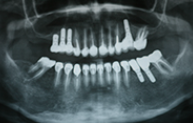

Cas cliniques

Chaque cas est unique nous essayons toujours de privilégier la meilleure solution pour le patient, d'abord d'un point de vue thérapeutique mais aussi d'un point de vue financier.

Ces cas cliniques sont une illustration pédagogique de traitements odontologiques. Leur objectif est de mettre en image des soins dentaires pour une meilleure compréhension de ceux-ci.